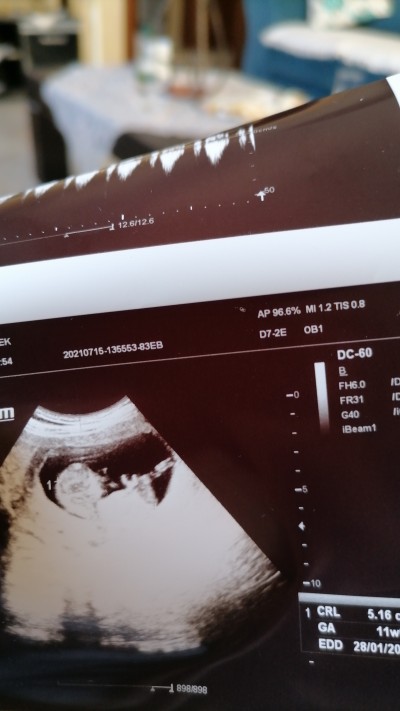

Merhaba anneler ve anne adayları. Fotoğrafta bebegimin cinsiyeti erkek denildi. Fakat bir sonraki kontrollerde bacakları hep kapalıydı ve kesin olmamakla birlikte kız tahmininde bulunuldu. Sizce ?

Gebelik haftası 35

Canim bana 11+5 de cikinti var ama  kordon olabilir dedi sonrada erkek diye gosterdi haftan 35  ayrintilida faln soylemediler